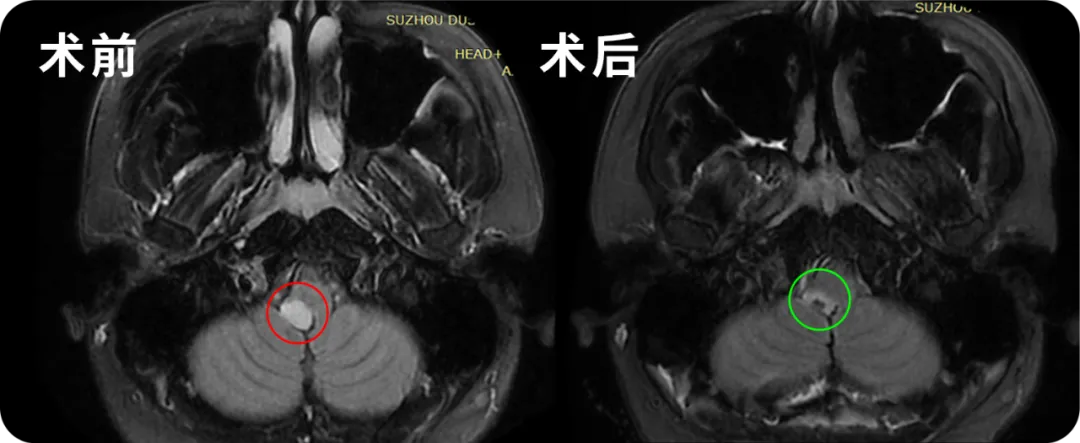

經(jīng)過術(shù)前精心準(zhǔn)備和反復(fù)討論,巴特朗菲教授帶領(lǐng)國內(nèi)神經(jīng)外科手術(shù)團隊奮戰(zhàn)。在神經(jīng)電生理監(jiān)測的密切配合下,巴教授根據(jù)周圍解剖結(jié)構(gòu)定位,盡最大的努力在保護正常功能的情況下切除腫瘤。在這場延髓膠質(zhì)瘤“殲滅戰(zhàn)”中,中外專家聯(lián)合手術(shù)取得完勝!手術(shù)為患者切除延髓膠質(zhì)瘤,且通過手術(shù)明確了病理性質(zhì),這也為后續(xù)治療提供了準(zhǔn)確方向。

川川的病理結(jié)果出來了,低級別膠質(zhì)瘤,傾向WHO 1級。成功的手術(shù)加上1級膠質(zhì)瘤的病理結(jié)果,意味著他將獲得良好的預(yù)后生存期。5年漫長的持久戰(zhàn),如履薄冰,川川一家人的心里終于可以稍微放松一些。